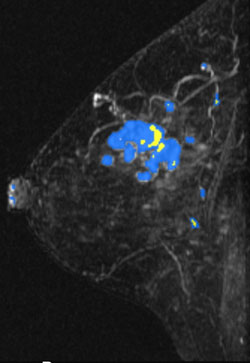

MR Angiomap

A right breast invasive lobular cancer (Estrogen Receptor/Progesterone Receptor +, Her-2 neu -).

MIP (Maximum Intensity Projection) image of MR

MIP (Maximum Intensity Projection) image of MR shows the known cancer: irregularly marginated mass in the upper outer to central breast. Satellite subcentimeter nodules are present anteromedially and posteriorly.